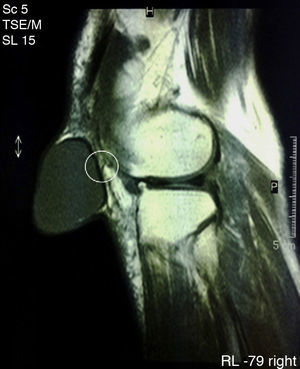

Finally, we performed magnetic resonance imaging (MRI) (Fig. 3) which confirmed the diagnosis of a cystic tumor but was unable to identify any communication with the prepatellar bursa, although it recognized a small non-communicating fold in the rear wall thereof. The anatomy of the rest of the knee was unremarkable except for characteristics associated with the age of the patient.

Synovial cysts are usually benign entities located outside the joint capsule but anatomically related to it by means of small channels that can be permeable or obliterated.1,5 In our case, we identified a fold of the posterior wall of the cyst which could be the remnant of a canal structure, now obliterated, that connected the cyst with the joint (Fig. 3). Synovial cysts are caused by mucinous degeneration, trauma or tumors.1 For any of these reasons, a shift of synovial fluid from regions of high to low pressure causing a progressive mobilization of the synovial tissue and its eventual outgrowth outside the capsule.2 Once this phenomenon occurs, the liquid may organize or move freely from the joint to the cyst through a channel with a permeability can be permanent, episodic or short lasting.6 The displacement of fluid in one direction or another conditions an increase or decrease in the size of the cavity.2